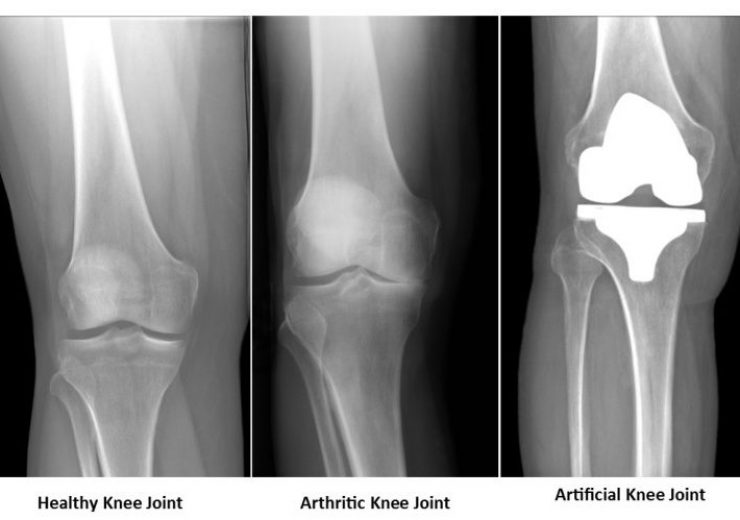

- એક્સ-રે